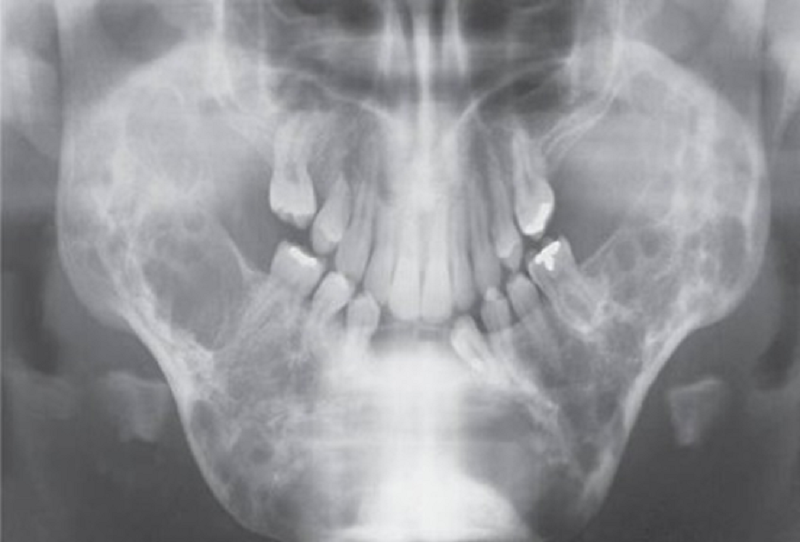

{"name":"Oral Path ID Chapter 6-9", "url":"https://www.quiz-maker.com/QPREVIEW","txt":"This condition is linked with Keratinosis of the palms of the hands & the soles of the feet. Individuals with this condition are likely to experience tooth mobility and premature tooth loss., This Term is used to describe The Appearance of type III (hypomaturation) Amelogenesis Imperfecta, Radiographs of a person with this condition appear to have a multilocular or “soap bubble” appearance","img":"https://www.quiz-maker.com/3012/CDN/92-4508546/final-pic-1.png?sz=1200"}